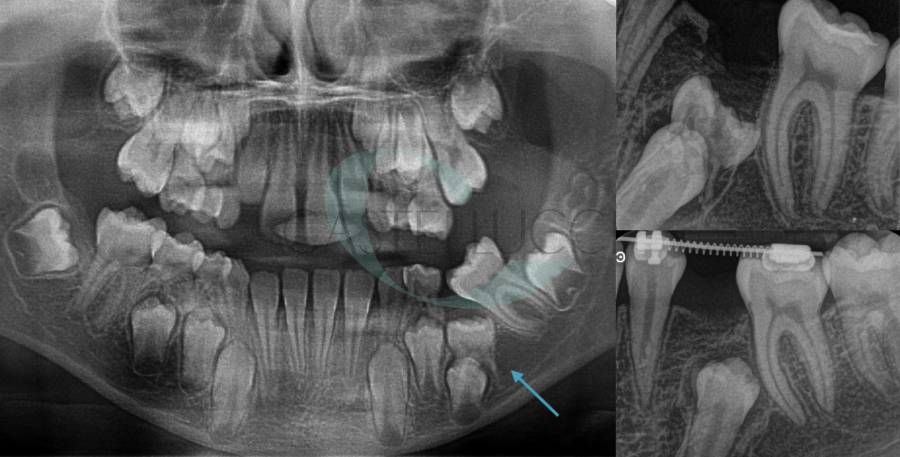

• Disinclusione chirurgica degli elementi dentari permanenti ritenuti